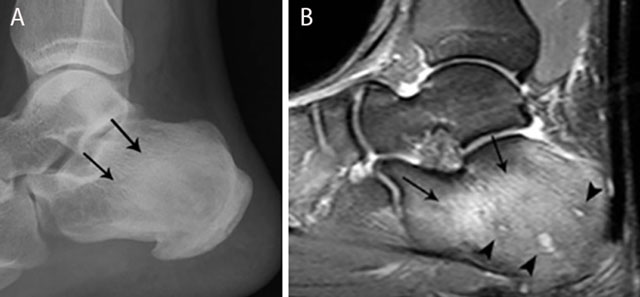

Figure 12

Chronic osteomyelitis of the calcaneus. Plain radiograph (a) and sagittal Fat–Sat T2–WI (b). Plain radiograph (a) shows inhomogeneous sclerosis (black arrows) in the calcaneus. Bone marrow edema (black arrows) is seen on MRI imaging (b), representing active infection. Note also the presence of small micro-abscesses (black arrowheads).